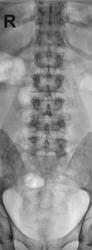

Травма (ДТП) в мае месяце. На контроль пришел на костылях.

Травма (ДТП) в мае месяце. На контроль пришел на костылях

пишут не рентгенологи, а клиницисты. О сдавливании элементов хвоста, кроме клиницистов, могут еще судить магниторадиологи. Наш (общий на всех) термин - стеноз позвоночного канала. Еще надо не лениться и указать степень компрессии компрессии тела - легкая (20-25%), умеренная (25-40%), выраженная (больше 40%). А также замерить расстояние между основаниями дуг позвонков в прямой проекции - у L4 оно явно шире, и тогда в дополнение к перелому тела добавится перелом дуги и термин "нестабильный". Для полной красоты следует указывать угол кифотической деформации; критическими значениями являются:  для шейного отдела - 11º,  для грудного – 40º,  для поясничного - 25º

а здесь еще и переломовывих L4. а перелом еще и оскольчатый. с такой картиной можно утверждать что инвалидизация пациенту светит.А в S4 я перелома не вижу.